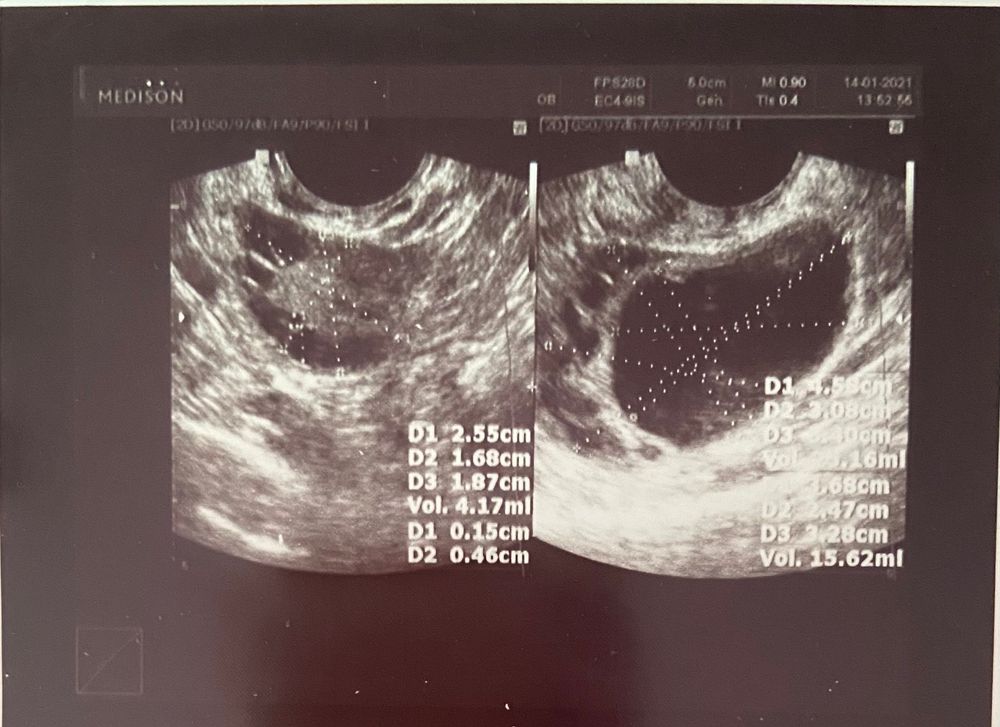

Фолликулярная киста. Сделали лапароскопию Изображение